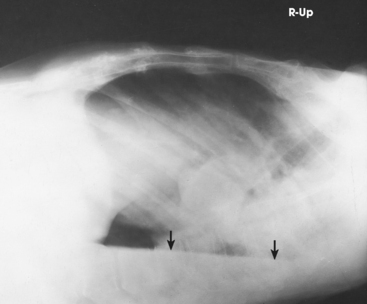

Structures shown: AP or PA projection obtained using the lateral decubitus position shows the change in fluid position and reveals any previously obscured pulmonary areas or, in the case of suspected pneumothorax, the presence of any free air (Figs. 10-62 to 10-64).

Fig. 10-62 AP projection, right lateral decubitus position, showing a fluid level (arrows) on the side that is down. Note the fluid in the lung fissure (arrowhead). Note correct marker placement, with the upper side of the patient indicated.

Fig. 10-63 AP projection, left lateral decubitus position, in same patient as in Fig. 10-64. Arrows indicate air-fluid level (air on the side up). Note correct marker placement, with upper side of the patient indicated.